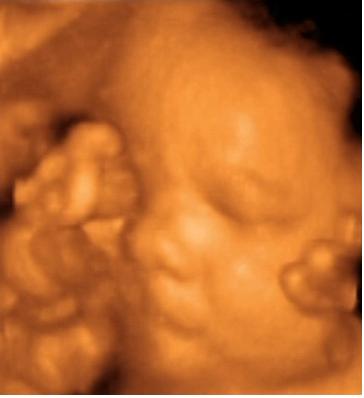

A lényeg. Lányunk lesz. Bár számomra ez nem volt egyértelmű a kép alapján...talán nektek az lesz. Már most kész óriás, 2703 g. Gyönyörű babó, bár most nem voltunk olyan szerencsések, mint a múltkor és folymatosan eltakarta magát. Nagyon fájt a szívem amikor láttam, hogy mennyire össze van "hajtogatva" szegénykém. a bal lába a homlokánál van :(. No de ez van. Remélem azért nem annyira rossz neki.

Küldöm a képeket is.

Nekem egyértelmű a nunika!:)

De jó,és nagyon jók a képek!Örülök,hogy a vágy is teljesült,és kislány lett!

Gratula a lánykához! Ne aggódj, ő abban a pozícióban érzi jól magát! És egyébként is olyan lányos arca van...és milyen pici és széles kis orra. :) Egyébként ahogy Doren is írta, én is elcsodálkozok, amikor Peti elnyújtózik, hogy hogy a fenébe fért el bennem...